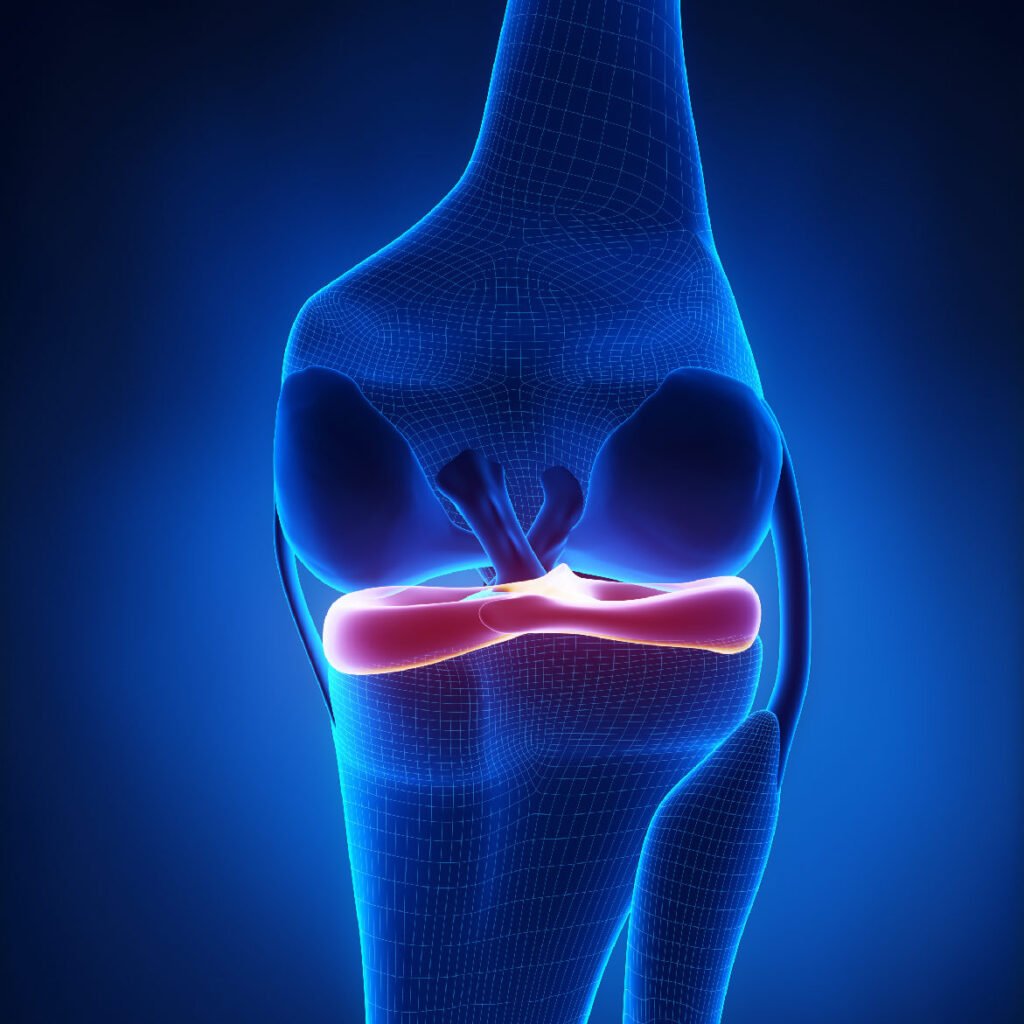

Les ménisques, des structures en forme de croissant entre le fémur et le tibia, servent d’amortisseurs et de stabilisateurs. Les ligaments et tendons assurent la stabilité et le mouvement de l’articulation.

QU’EST-CE QU'UNE LÉSION MÉNISCALE ?

Une lésion méniscale fait référence à une déchirure ou un dommage subi par l’un des ménisques du genou, qui sont des structures cartilagineuses en forme de croissant, situées entre le fémur et le tibia. Les ménisques jouent un rôle clé dans l’absorption des chocs, la stabilité et la répartition des forces au sein de l’articulation du genou.

Il existe 2 type de lésions méniscales :